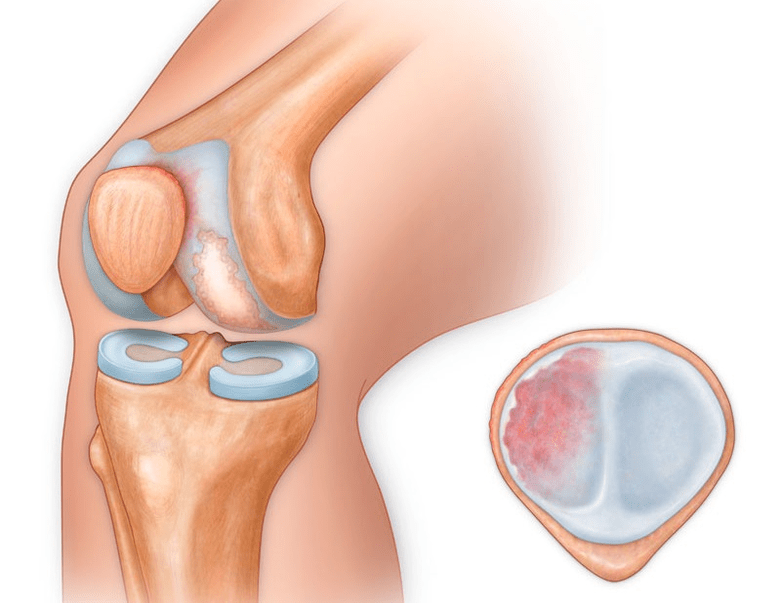

In addition to the inside or outside of the knee, arthrosis can also affect the surface between the patella and the intercondylar groove of the femur.This option is calledpatellofemoral arthrosis.

The cause is usually subluxation, fracture, or lateralization of the patella.

In the second stage, the cartilage layer becomes thinner, and in some places is completely absent.Osteophytes appear along the edges of the articular surface.The qualitative and quantitative characteristics of the synovial fluid of the joint changes - it becomes thicker, more viscous, which leads to a deterioration in its nutritional and lubricating properties.The pain is more prolonged and intense, and a throbbing sound often appears when moving.There is little or moderate movement restriction and little joint deformity.Taking analgesics helps relieve pain.

Lack of cartilage in the most affected areas, severe sclerosis (hardening) of the bones, many osteophytes and sharp narrowing or absence of the joint space.The pain is almost constant, the gait is disturbed.Mobility is very limited, and joint deformation can be seen.NSAIDs, physiotherapy and other standard methods of treating knee arthrosis are ineffective.